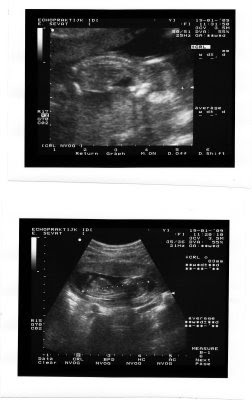

Tatiana is 3 1/2 maand zwanger!

Ha iedereen! We willen jullie allemaal laten weten dat Maëlle een klein broertje of zusje gaat krijgen ;-) Hier is de eerste "foto" van het kleintje (alias Lievertje)